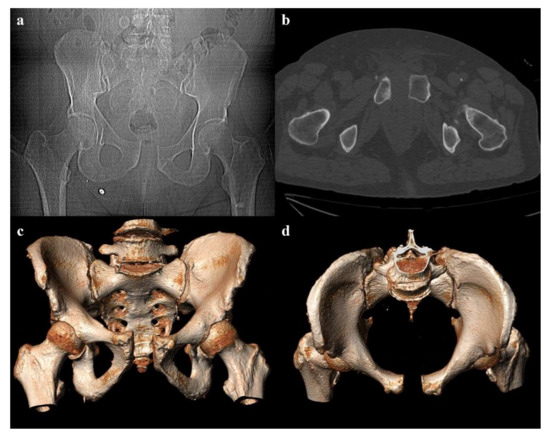

Review

Imaging Review of Pelvic Ring Fractures and Its Complications in High-Energy Trauma

by Edoardo Leone, Andrea Garipoli, Umberto Ripani, Riccardo Maria Lanzetti, Marco Spoliti, Domenico Creta, Carolina Giannace, Antonio Galluzzo, Margherita Trinci and Michele Galluzzo

Pelvic ring fractures are common in high-energy blunt trauma, especially in traffic accidents. These types of injuries have a high rate of morbidity and mortality, due to the common instability of the fractures, and the associated intrapelvic vascular and visceral complications. Computed tomography [...] Read more.

Pelvic ring fractures are common in high-energy blunt trauma, especially in traffic accidents. These types of injuries have a high rate of morbidity and mortality, due to the common instability of the fractures, and the associated intrapelvic vascular and visceral complications. Computed tomography (CT) is the gold standard technique in the evaluation of pelvic trauma because it can quickly and accurately identify pelvic ring fractures, intrapelvic active bleeding, and lesions of other body systems. To properly guide the multidisciplinary management of the polytrauma patient, a classification criterion is mandatory. In this review, we decided to focus on the Young and Burgess classification, because it combines the mechanism and the stability of the fractures, helping to accurately identify injuries and related complications. Full article